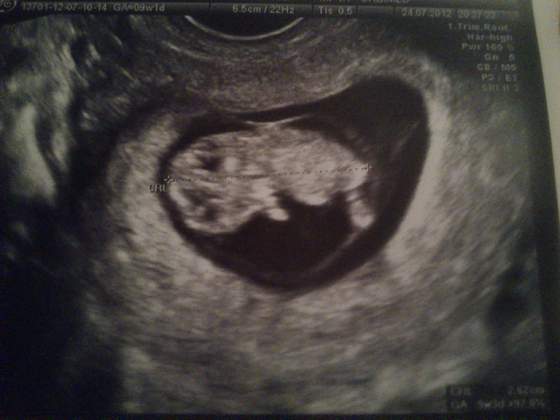

Zobacz załącznik 485274

Oto mój bobasek ma aż 2,62cm wzrostu :-)

Sylwia śliczny bobasek a termin masz dzień przede mną z OM